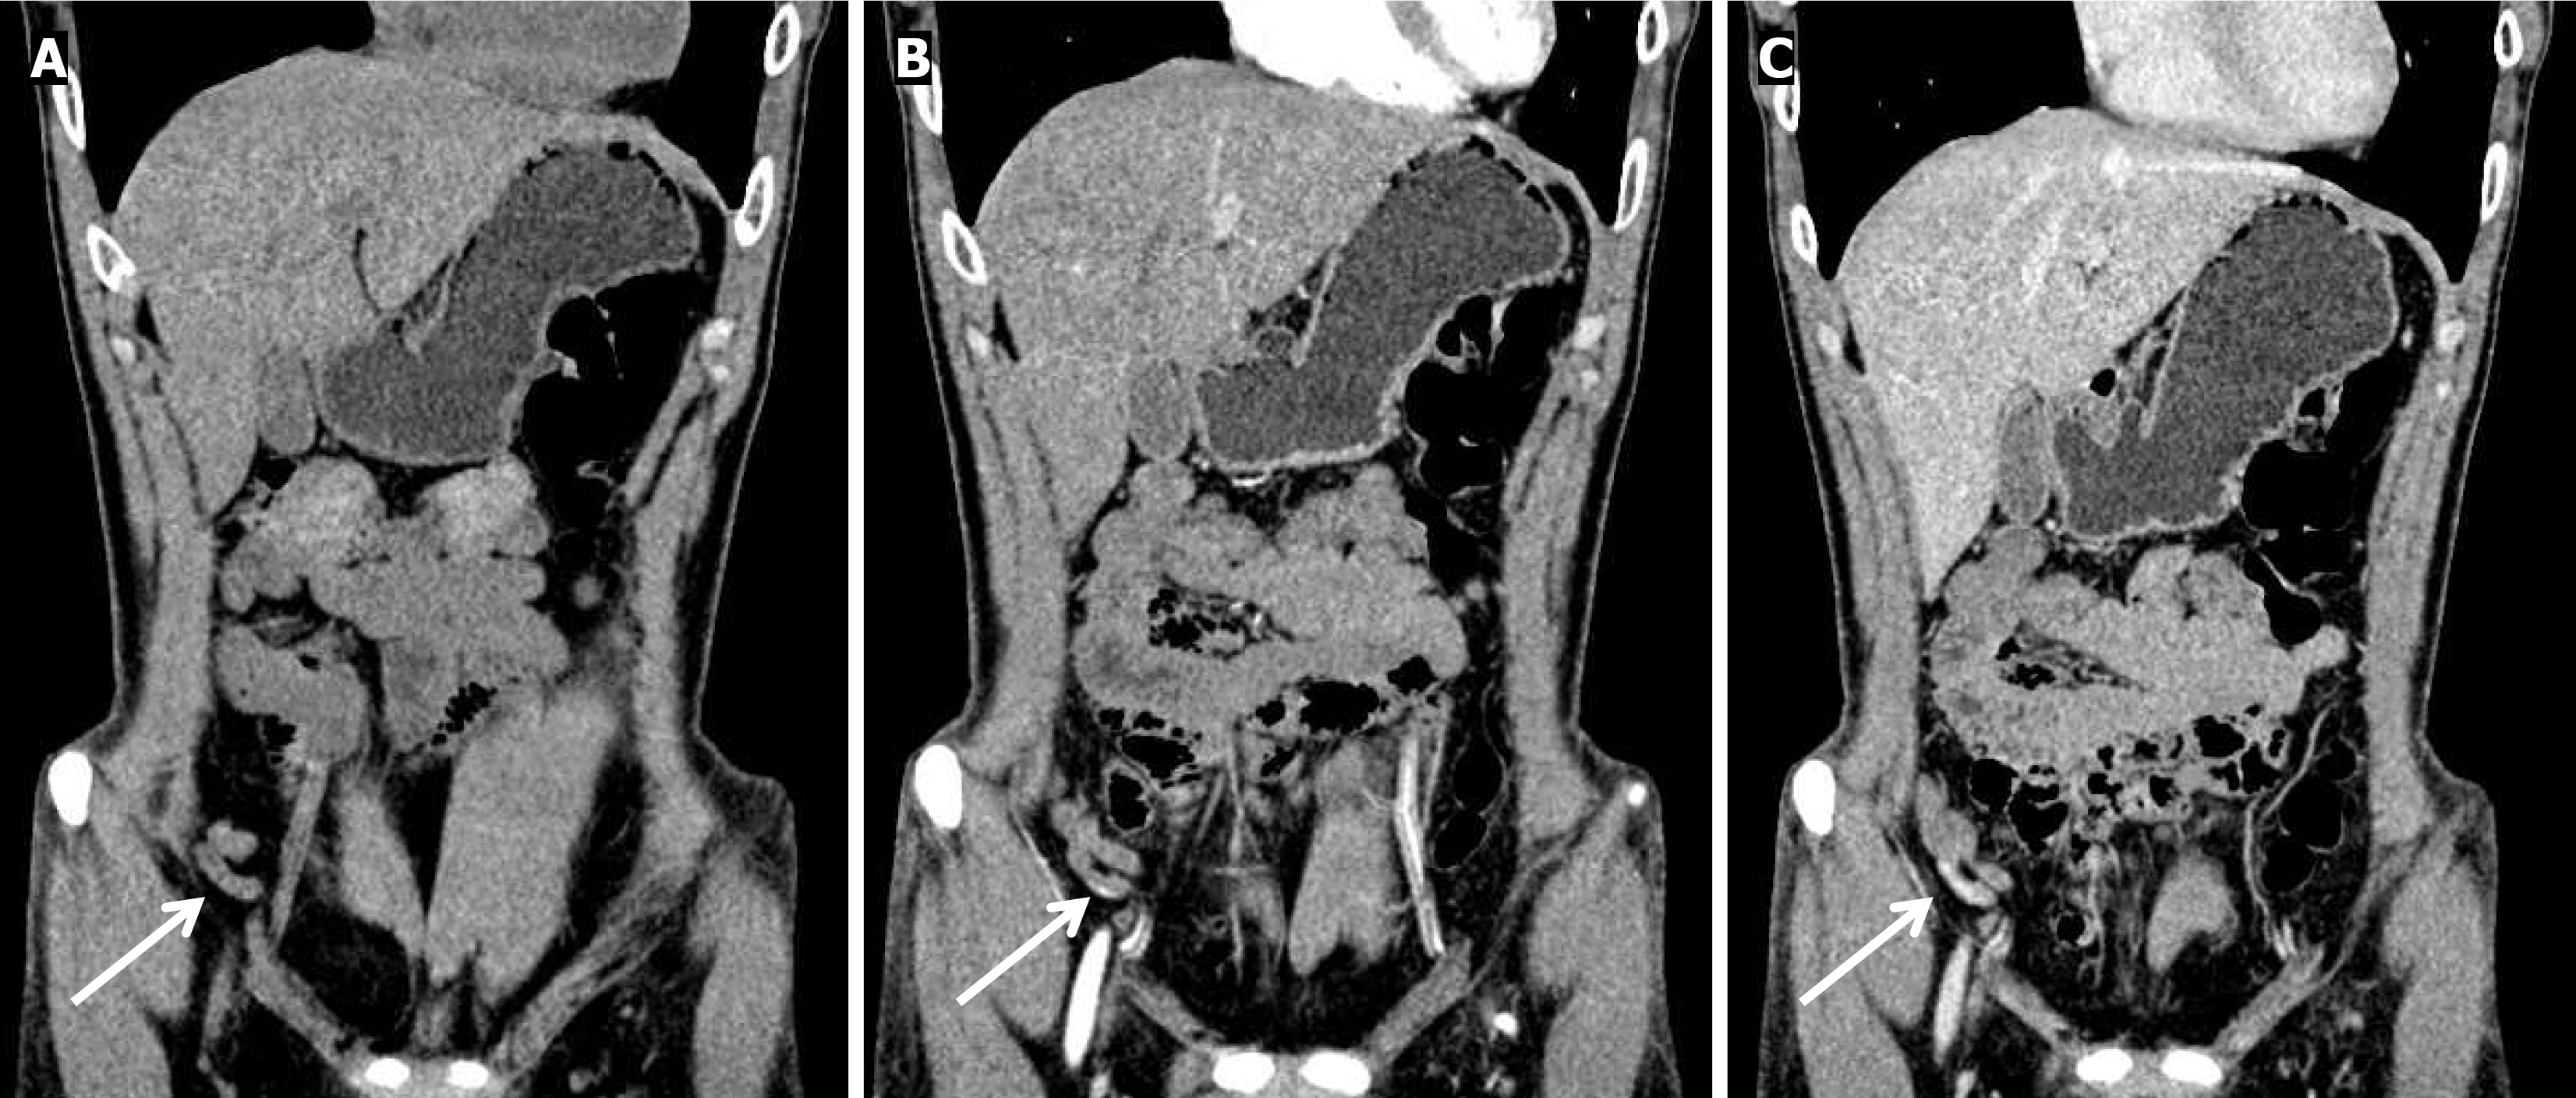

On January 7, 2025, colonoscopy was performed after bowel preparation which revealed a small amount of dark red blood in the colon and minimal bright red blood in the terminal ileum. After repeated water flushing, the mucosa of the terminal ileum appeared smooth, with no blood in the proximal intestinal lumen. On careful examination, fresh bleeding was noted from the appendiceal orifice (Figure 1). Following colonoscopy, emergent computed tomography angiography (CTA) was performed, which demonstrated active bleeding at the appendiceal orifice (Figure 2).

Figure 1

Figure 1 Colonoscopic examination shows bright red blood in the ileocecal region, and a blood clot and blood flowing from the appendix orifice. A: Blood clot at the appendiceal orifice (arrow); B: Extravasation of blood from the orifice of the appendix after flushing (arrow).